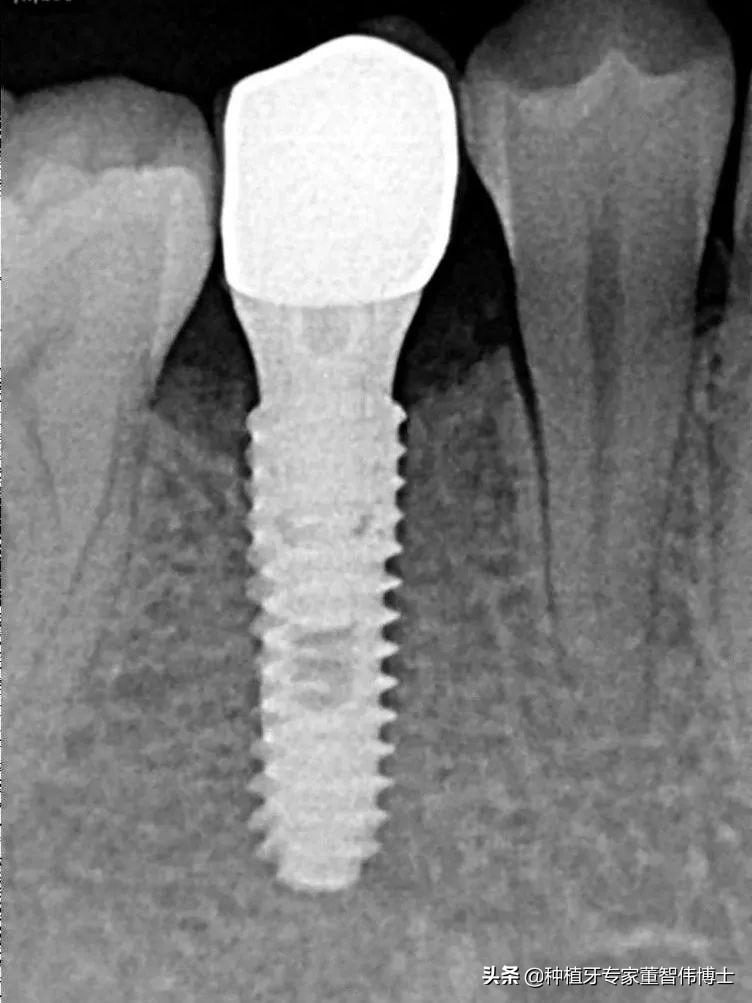

种植体术后3月颊面观可见种植体愈合良好,X线片可见,种植体位置、角度、深度控制良好

术后X线片显示种植体位置好,修复体形态恢复良好